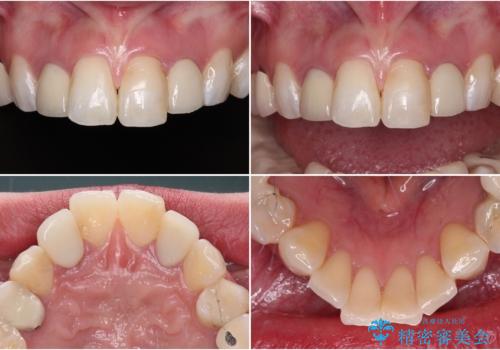

金属の見えてしまったクラウン セラミッククラウンで自然に

- クラウンから金属の土台が見えてきてしまったとのことで、作り替えを希望して来院された患者様です。

前歯や金属が露出している歯、痛みを感じる歯を中心に、オールセラミッククラウンにて補綴治療することとしました。

以前はセラミッククラウンのフレームとして金属が使用されており、歯肉の経年変化やセラミックのすり減りなどにより、金属が見えるようになってくることがあります。

現在は金属の代わりに強化セラミックを使用したオールセラミッククラウンが主流です。金属色が気になる方はご相談ください。